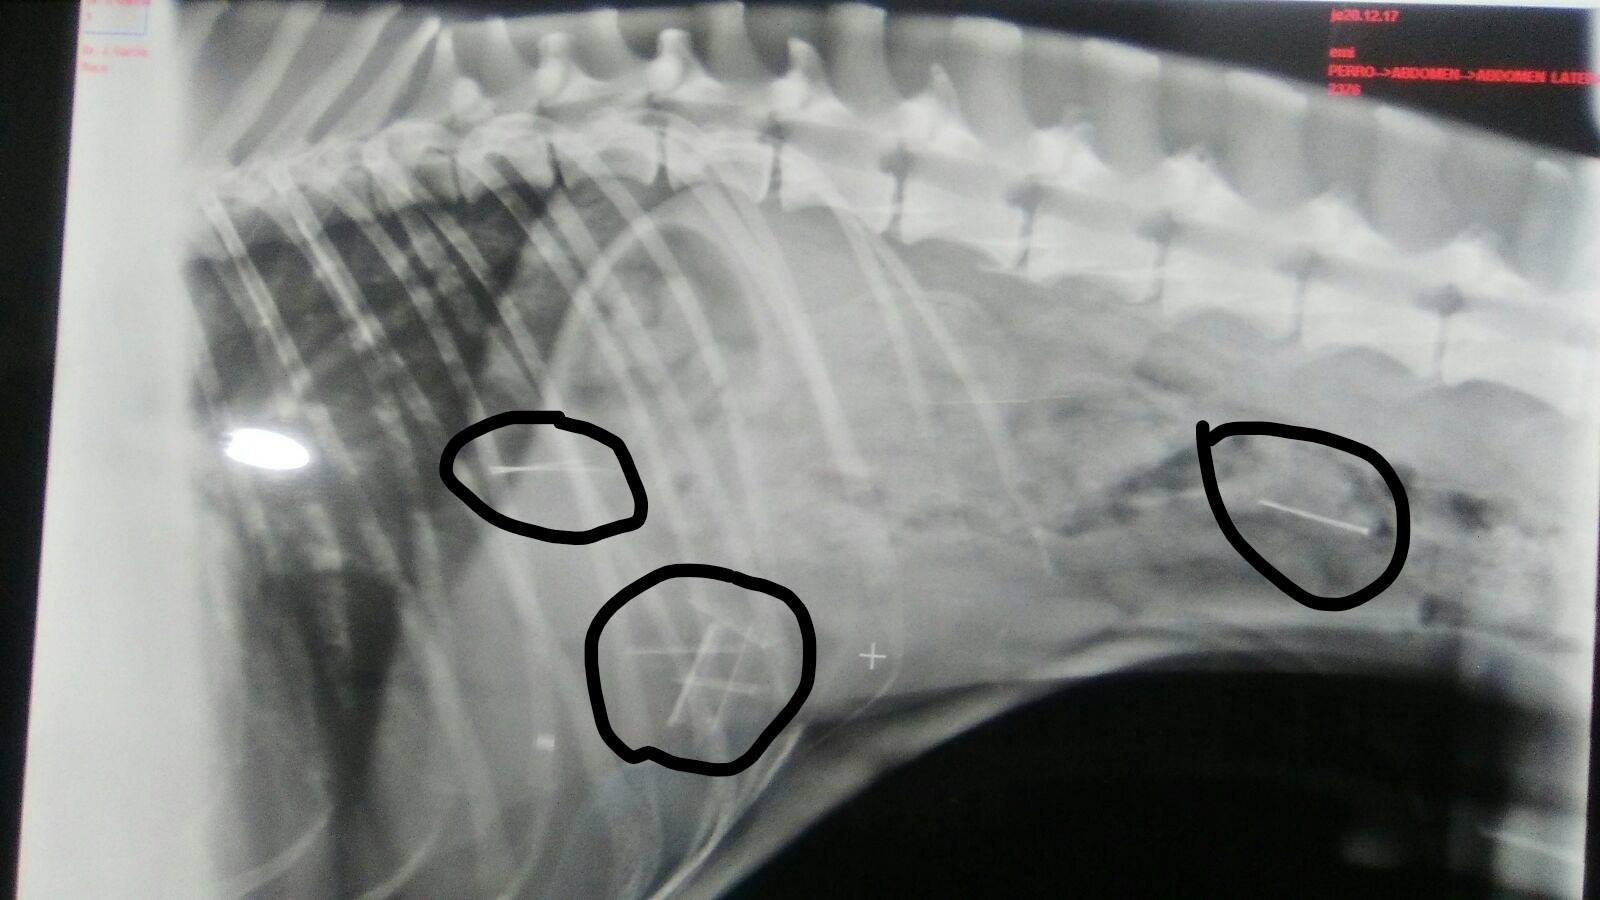

Desde entonces comenzó a alertar a sus conocidos. Pero al día siguiente, Flaco, el perro de Emi, comenzó a encontrarse mal. Ante la actitud del animal, y sabiendo que ella lo pasea "por esa zona", no dudó en llevarlo a un especialista. Efectivamente, tenía ocho clavos entre el intestino y el estómago. A pesar de ello, goza de una salud "aparentemente normal", pero solo ha logrado expulsar uno desde entonces y continúa con siete en su interior. Por ello, Ismael pide información con el objetivo de encontrar pistas que localicen al autor o autores de tan macabro plan, desde una visita al veterinario a un informe o una foto, "cualquier ayuda es buena", sentencia.

Jerónimo García, veterinario de la clínica Nueva Tavira que ha atendido al perro de Emi, advierte que "la vida de Flaco lleva corriendo peligro desde entonces, los clavos son objetos muy peligrosos porque, además de pinchar mucho, tiene todavía siete y son muy difíciles de localizar quirúrgicamente". A pesar de estar en sus días de vacaciones, no desconecta en ningún momento porque "es un caso muy delicado y que no te esperas". De hecho, no tiene dudas al afirmar que en este tipo de situaciones "si los dueños no están encima del animal se muere".